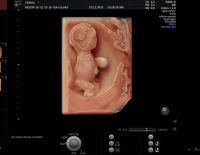

Siêu âm 5D những thông tin đầy đủ – hữu ích và cần thiết

Siêu âm 5D là một trong những hình thức siêu âm mà các mẹ bầu sẽ thực hiện trong quá trình thai kỳ. Tuy nhiên, nhiều chị em còn băn khoăn chưa hiểu rõ về hình thức siêu âm này ra sao? Vậy, bài chia...